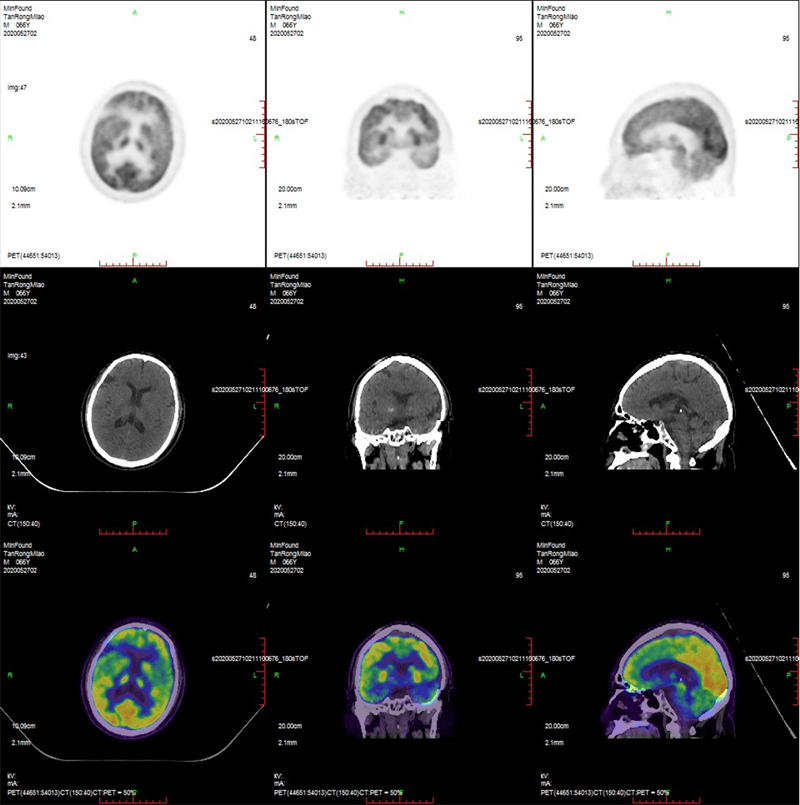

Clinical Gallery